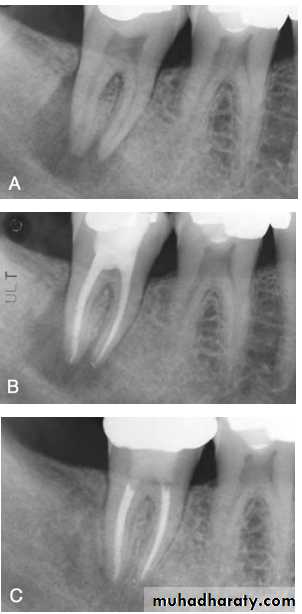

Classification of endodontic-periodontic lesions. (A) Primary pulpal infection can lead to chronic periradicular periodontitis by which a periapical radiolucency can develop and migrate cervically. Mandibular molars can also have accessory canals in lateral orientation or in the furcation area. These accessory canals can allow migration of the primary pulpal infection and cause secondary breakdown of the periodontium at their respective loci. (B) Primary periodontal infection can lead to extensive breakdown of alveolar crest bone that migrates from the cervical area to the apex. In these lesions, one would find generalized bone loss around a single tooth or that often could involve multiple adjacent teeth. Because of the pulpal-periodontal continuum through main root canal foramina or through accessory canals, extensive periodontal infection can cause irritation in the pulp tissues. (C) Both primary pulpal infection and primary periodontal infection can occur simultaneously in an “independent” endo-perio lesion, exhibiting the characteristics of both. (D) Primary pulpal and primary periodontal infections can occur extensively in this “combined” endo-perio lesion.